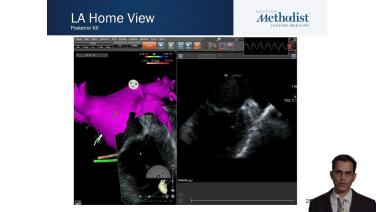

Transitioning from TEE to ICE by Integrating the CARTOSOUND® Module for Optimal LAA Visualization with Apoor Patel, MD

Atrial Anatomy for the Electrophysiologist